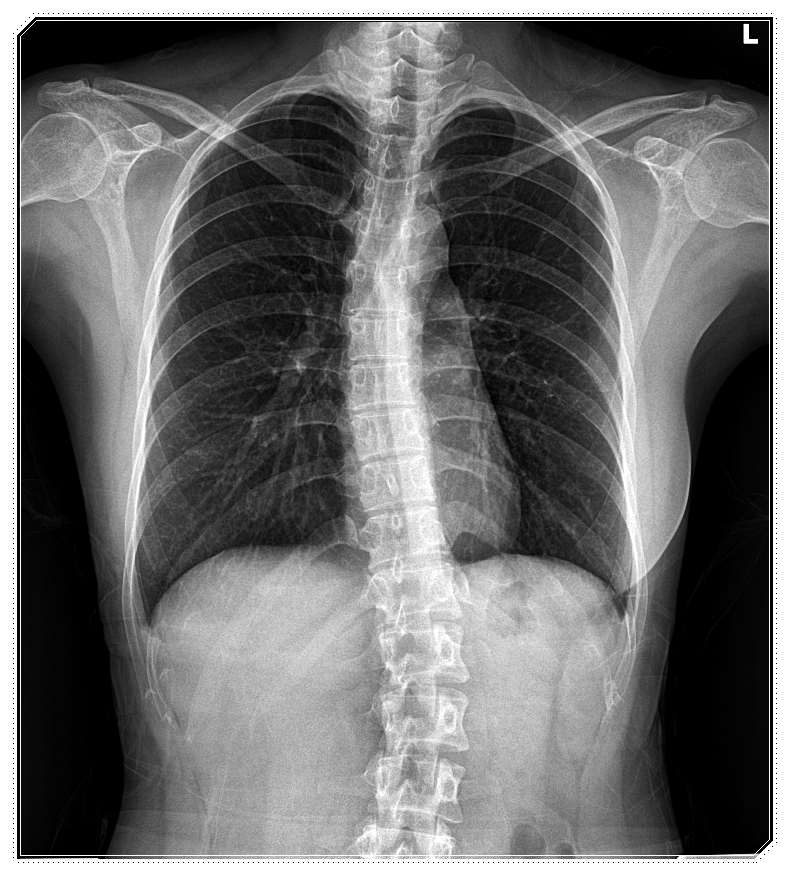

척추는 단순히 옆으로만 휘는 구조가 아닙니다.

사람마다 앞·뒤·옆으로 틀어지거나,

비틀리듯 꼬인 형태가 모두 다르게 나타나죠.

그래서 같은 ‘척추측만증’이라 하더라도

휘어진 각도와 방향, 회전 상태는 저마다 다른 양상을 보이게 됩니다.

이 때문에 척추의 변형은

평면적인 관점이 아닌, 3차원적인 구조로 이해하는 것이 중요합니다.